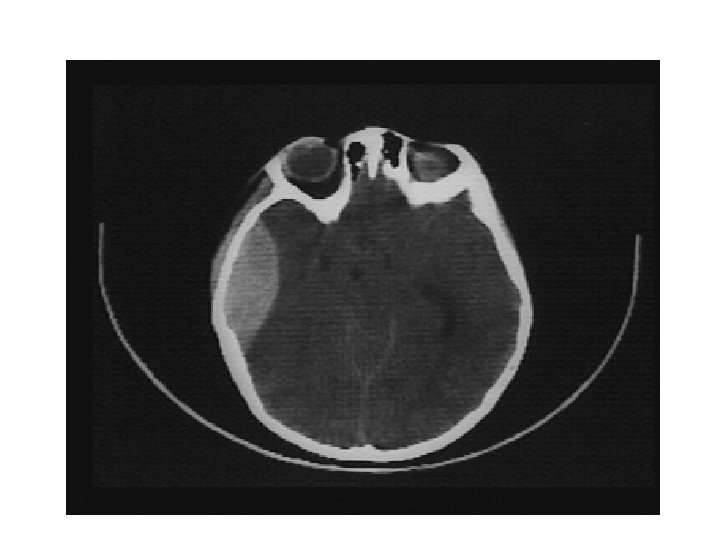

Les différentes lésions 2/2 • Hématome extra-dural – L'hématome extra-dural ou épidural est une accumulation de sang entre l'os du crâne et la dure-mère (enveloppe fibreuse du cerveau faisant partie des méninges). L'hématome extra-dural est une urgence chirurgicale absolue. Il se développe en quelques heures et peut entraîner la mort du patient par engagement cérébral si rien n'est fait. • Hématome sous-dural – Il s'agit d'un épanchement sanguin situé entre, en dehors la dure-mère, et en dedans l’arachnoïde. Il peut survenir de façon aiguë, au cours des heures suivant le traumatisme (hématome sous-dural aigu). Il est alors fréquemment associé à une contusion cérébrale dont peut dépendre le pronostic. Il peut aussi se constituer à bas bruit, et se démasquer quinze jours, voire des semaines après un traumatisme relativement peu important (hématome sous-dural chronique). • Hémorragie intracérébrale – Il s'agit d'un saignement à l'intérieur du parenchyme cérébral. • Hémorragie méningée – Une hémorragie méningée est observée dans 1/3 des traumatismes crâniens sévères. Elle peut être secondaire à la lésion d'un vaisseau méningé, ou bien à une suffusion hémorragique à partir d’un foyer de contusion du cortex cérébral.